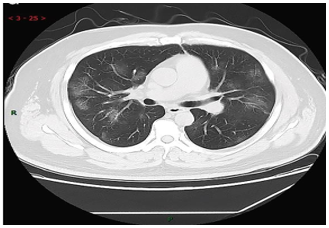

The chest CT scans testing method is one of the most useful methods for the detection of COID- 19 along with laboratory testing methods such as PCR, hematology tests, and rRT-PCR. In this regard,

Y. H. Jin et al [1] strongly suggested CT imaging for the diagnosis of COIVD-19. They reported that in the CT images of 54.2% COVID-19 patients, multiple, patchy, sub-segmental or segmental ground- glass density shadows in both lungs were observed (Figure 1). They also noted that the CT scans of 31.3% of severe patients infected with COVID-19 showed the patchy, multiple, and/or large patches of consolidation in lungs along with a honeycomb-shaped interlobular septal thickening or little grid- like in the lower and middle lobes.

Figure 1. CT image of 38 years old male with fever (39.3℃), dry cough and shortness of breath for 3 days (adopted from Y. H. Jin et al., 2020 [1]).